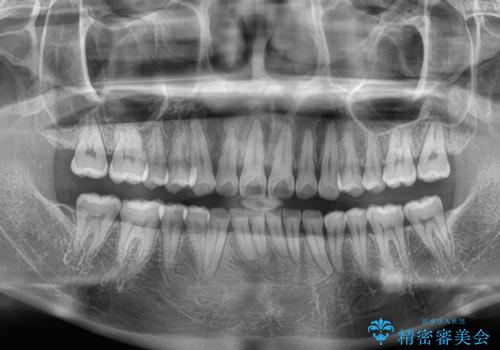

- 下顎前歯が完全に隠れてしまっていることを気にして来院された患者様です。

下顎の臼歯が手前に傾斜していることで咬み合わせが深くなってしまい、下顎前歯が見えないほどに上顎前歯が覆い被さっている状態でした。

下顎臼歯を起き上がらせるためにユーティリティーアーチを使用し、一気に深い咬み合わせを改善することができました。